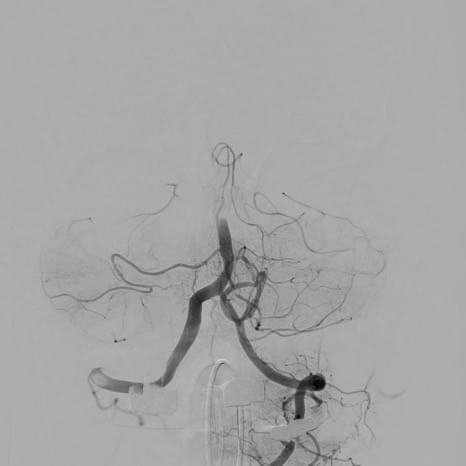

Our research seeks to advance our understanding of cerebrovascular disease and to develop new minimally invasive treatments for these diseases. We study ischemic and hemorrhagic stroke, cerebral aneurysms, delayed cerebral ischemia, cerebral arteriovenous malformations (AVMs), dural arteriovenous fistulae, and other vascular diseases of the brain. We use state-of-the-art neuroimaging techniques to non-invasively study these diseases, and we are developing future endovascular technologies to advance neurointerventional surgery.

Our clinical research team seeks to advance our understanding of ischemic and hemorrhagic stroke pathophysiology and improve the non-invasive imaging evaluation and endovascular treatment of these diseases. In addition, we are working to identify circulating biomarkers of acute and subacute cerebral ischemia to identify patients at risk of stroke before it happens.

Distinct intra-arterial clot localization affects tissue-level collaterals and venous outflow profiles

Faizy TD, et al. (2021) European Journal of Neurology. Dec;28(12):4109-4116. doi: 10.1111/ene.15079. Epub 2021 Aug 30.

Association of Venous Outflow Profiles and Successful Reperfusion After Thrombectomy

Faizy TD, et al. (2021) Neurology May 5;10.1212/WNL.0000000000012106.

doi: 10.1212/WNL.0000000000012106

Favorable Venous Outflow Profiles Correlate With Favorable Tissue-Level Collaterals and Clinical Outcome

Faizy T, et al. (2021) Stroke Mar 8;STROKEAHA120032242.

doi: 10.1161/STROKEAHA.120.032242.Online ahead of print.

Thrombectomy for acute ischemic stroke in nonagenarians compared with octogenarians.

Sussman ES, Martin B, Mlynash M, Marks MP, Marcellus D, Albers G, Lansberg M, Dodd R, Do HM, Heit JJ. (2020) Thrombectomy for Acute Ischemic Stroke in Nonagenarians Compared to Octogenarians. JNIS 12:266-270.